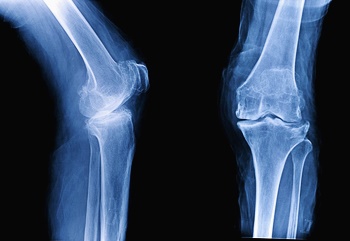

골관절염은 퇴행성 관절 질환으로 사용 정도에 따른 점진적인 관절연골의 소실, 또는 변화되는 증상을 동반합니다. 우리 몸의 관절에는 충격을 흡수하는 관절연골이 있는데요. 이러한 연골의 변화로 관절을 구성하는 뼈, 인대, 관절막 등에 2차적인 손상이 생겨 통증이나 기능 장애를 일으킵니다.

대표적인 증상은 관절의 통증입니다. 특히 무릎의 경우 계단을 오르거나 내릴 때 통증이 심해집니다. 증상이 진행되면 무릎에 물이 차서 하루 종일 통증이 생길 수 있는데요. 척추 관절, 고관절, 손가락 관절 등 다양한 부위에 발생할 수 있고 통증을 동반합니다. 손가락 마디에 발생하는 경우 손가락 마디가 굵어지기도 합니다.